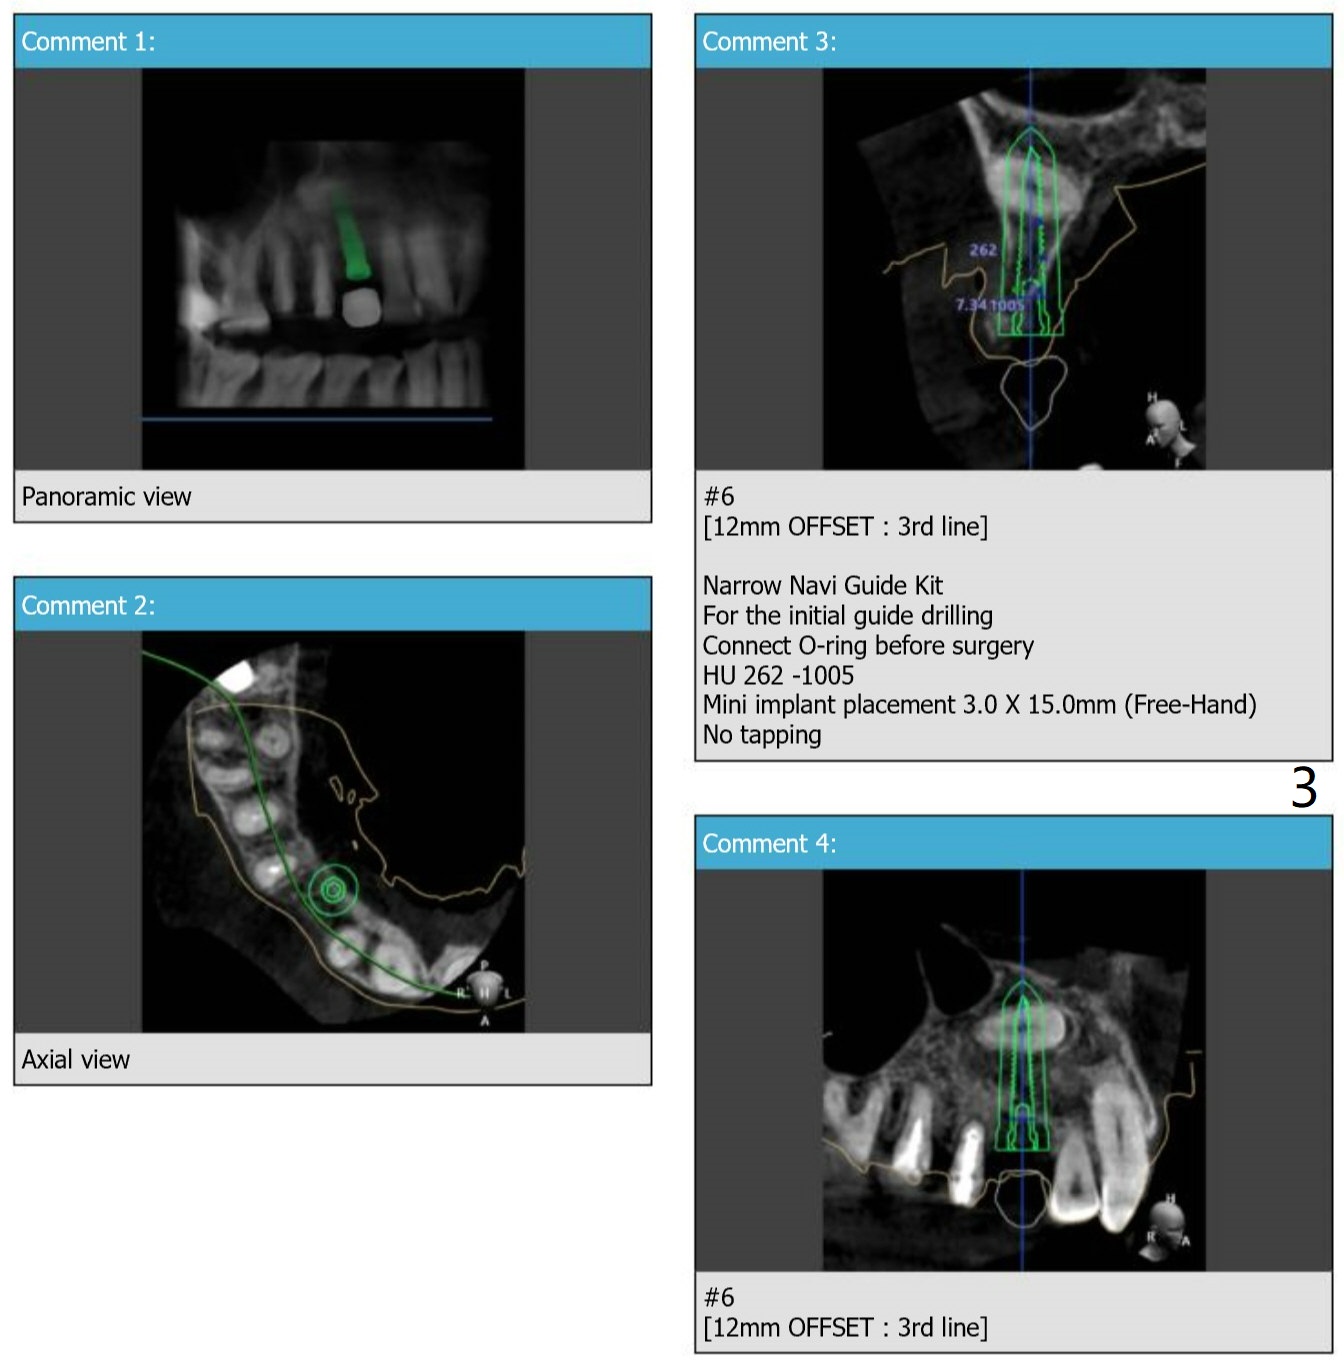

Partially Guided Surgery

Because of the narrow ridge and short bone, try in the guide, anesthetize (double anesthetics), start initial osteotomy with the guide and lay flaps for #6 impacted tooth removal. Use IS mini implant kit to finish the osteotomy free hand, hopefully entering the upper border of the extraction socket for 2-pointed fixation. Find the surgical stent for possible new temporary FPD.